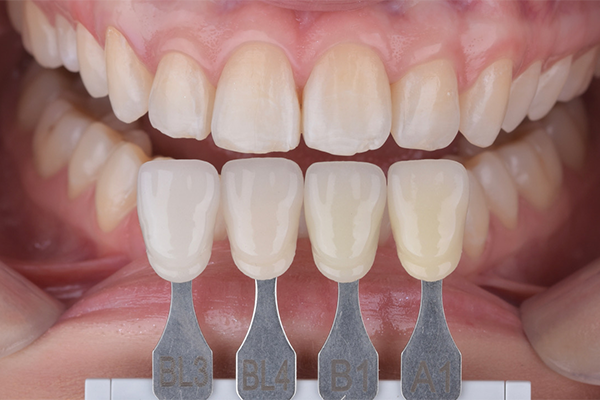

Na primeira consulta, foi realizada a profilaxia dos arcos dentários, com o objetivo de remover biofilme e facilitar a avaliação da coloração dental. Na consulta subsequente, foi realizada a mensuração da cor inicial dos dentes utilizando a escala de cor A-D. Foram identificadas as tonalidades A2 para os incisivos centrais superiores e A3 para os caninos superiores.

O protocolo completo incluiu 3 sessões de clareamento em consultório e 11 sessões de clareamento caseiro, realizadas ao longo de 14 dias. Como resultado, observou-se uma mudança significativa na coloração dental, passando das tonalidades A2 e A3 para BL4. Importante destacar que a paciente não apresentou qualquer episódio de sensibilidade dental durante todo o tratamento.

3 e 4 | Aspecto inicial, seleção de cor.

8 e 9 | Aspecto final, seleção de cor.